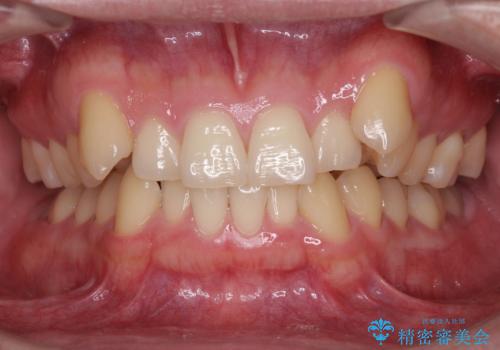

- 上顎の八重歯と前歯のデコボコを気にして来院された患者様です。

八重歯の移動量が多く、インビザライン単体での治療は困難と判断し、補助装置により八重歯移動後にインビザラインを用いることとしました。